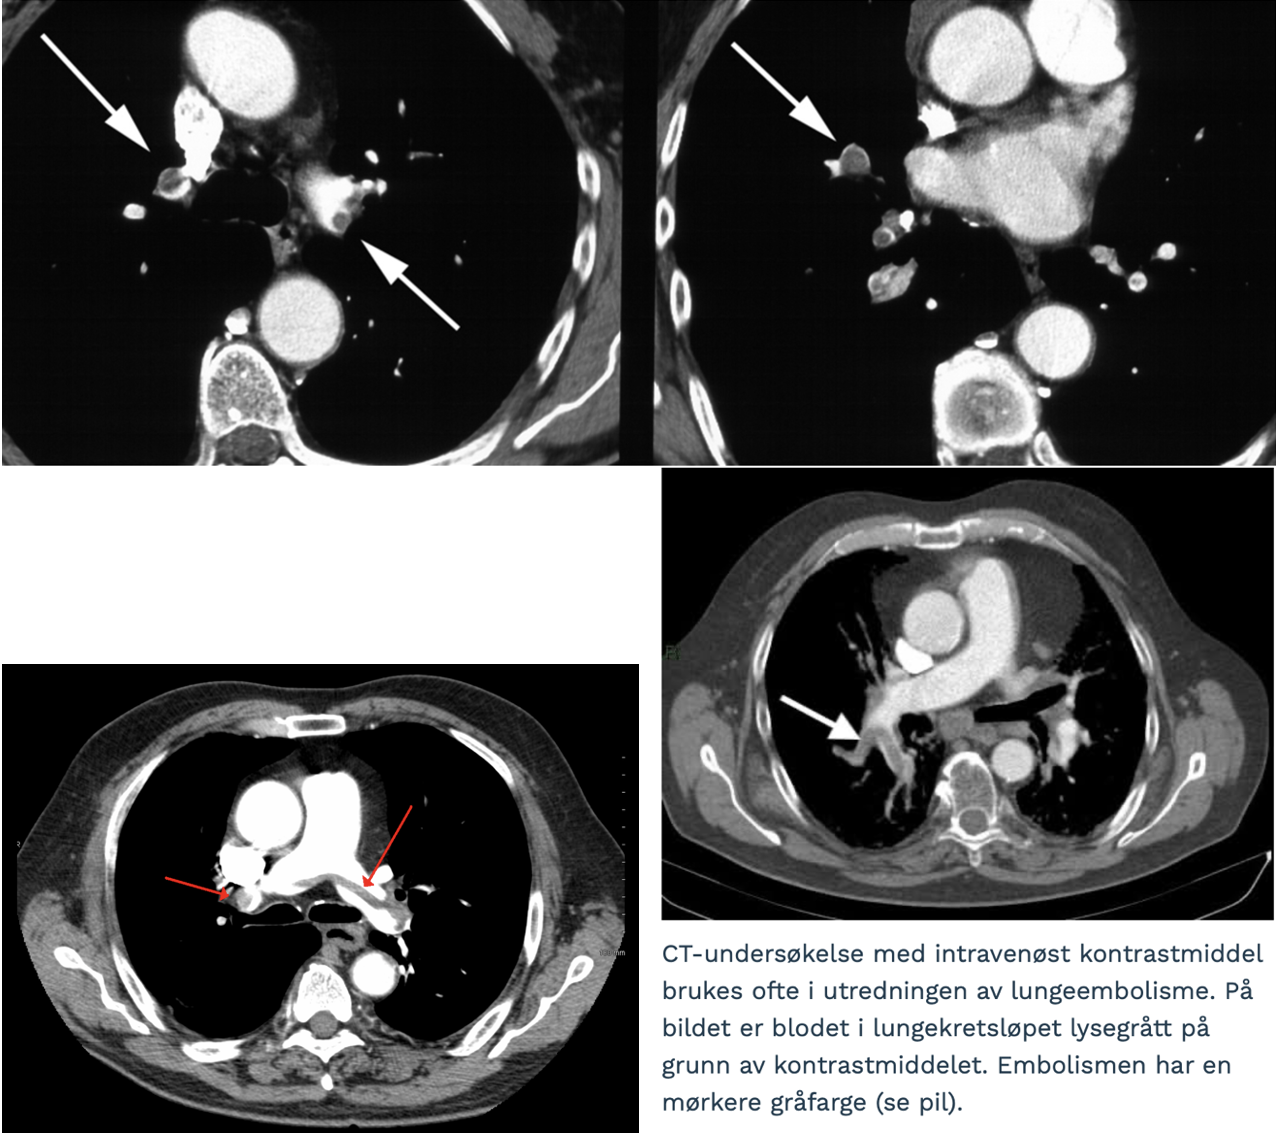

Lungeemboli:

- Embolier (mørke) omsluttet af blod (lyst)

Diagnose?

Lungeemboli